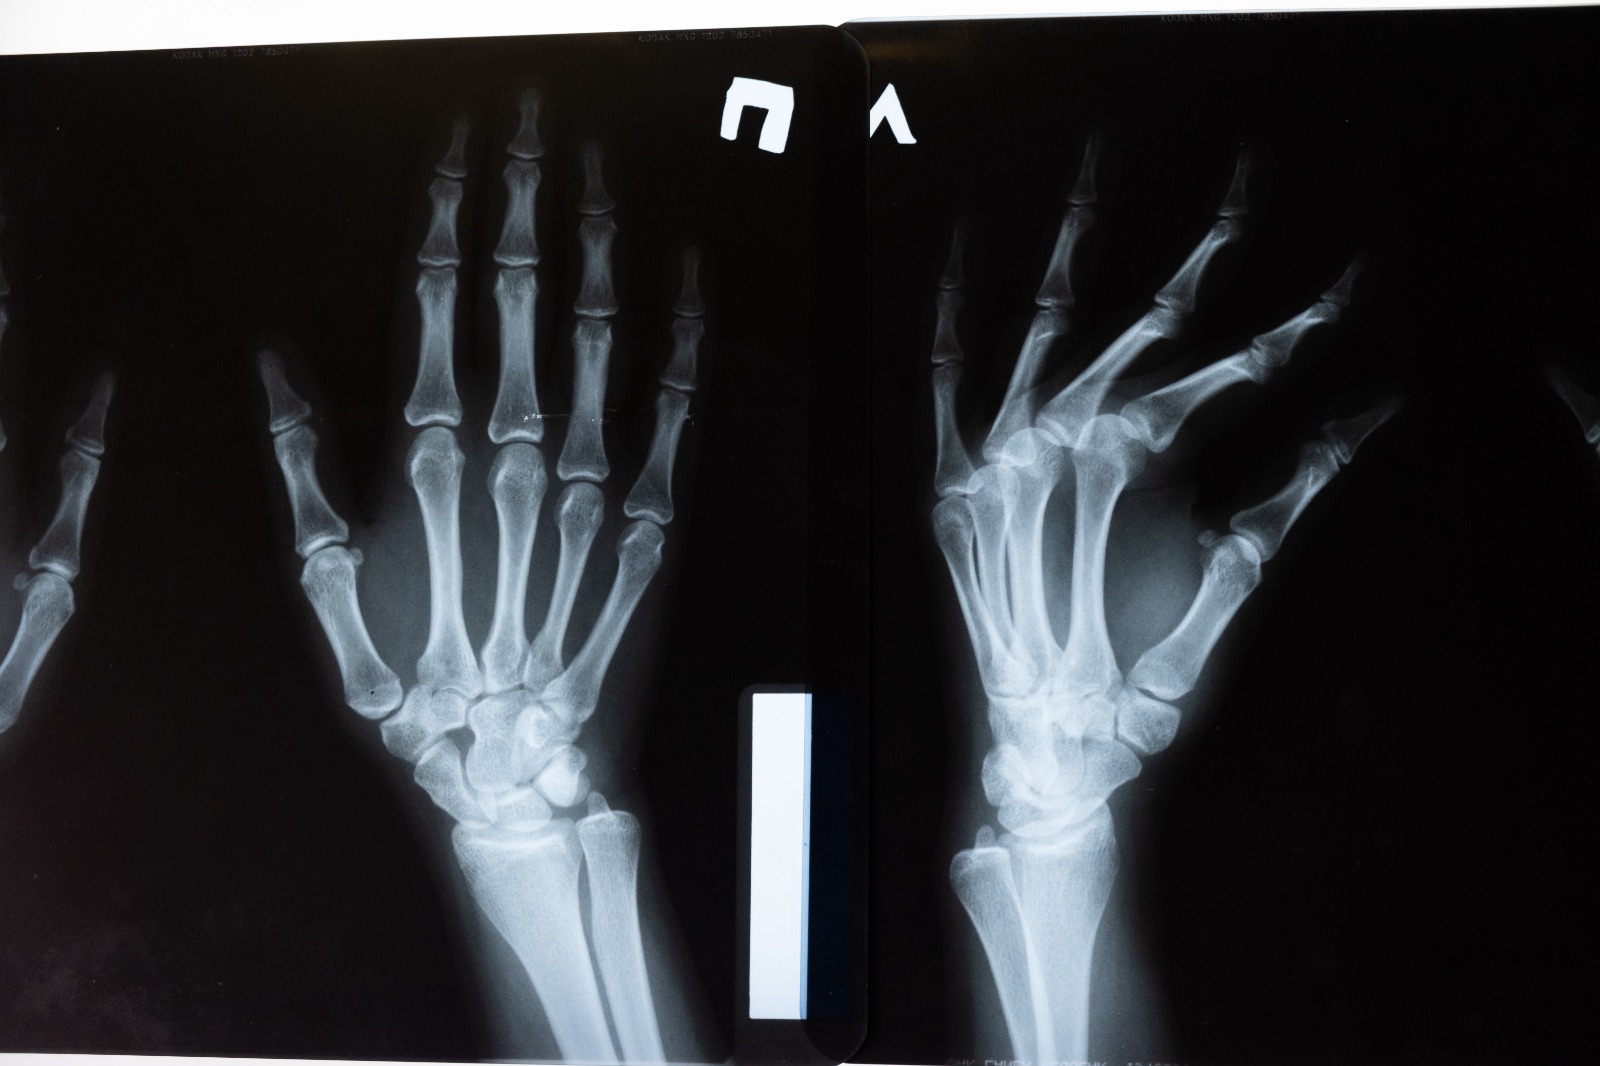

Osteoporoz, kelime anlamı “kemik erimesidir“. Kadınlarda menopoz döneminde, östrojen azalmasıyla birlikte kemiklerden kalsiyum çekilmeye başlar. Kalsiyum çekilmesi de kemiklerde D vitamini ve fosfor dengesini  olumsuz yönde etkiler.